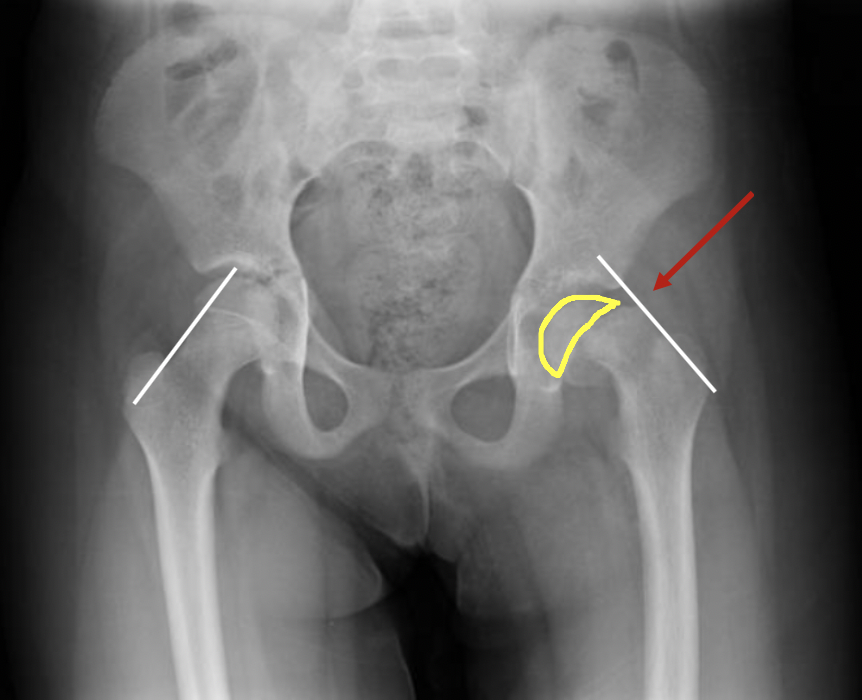

Диагностика ТБС рентгеном и асептический некроз: особенности лечения

Раздел: Снимки-откровения